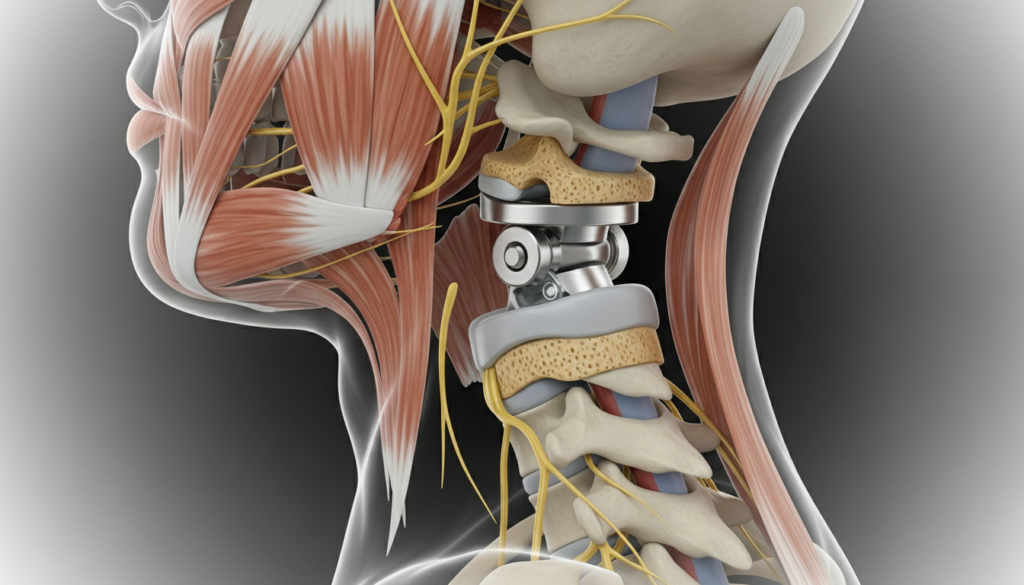

This procedure involves the removal of a damaged cervical disc and replacement with an artificial disc. It aims to relieve pain and restore motion in the neck.

Cervical disc replacement surgery is a surgical procedure that removes a damaged cervical disc in the spine and replaces it with an artificial disc to relieve pain and restore normal function.